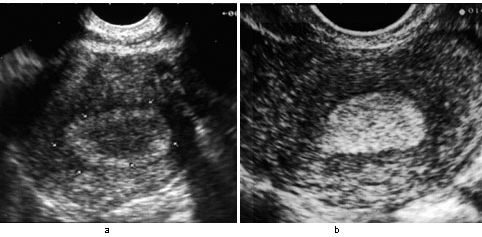

Endomètre sécrétoire